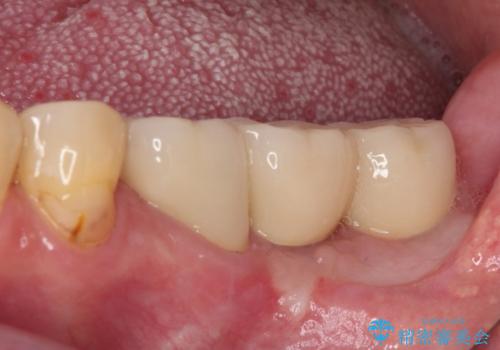

並行して左下にはインプラントを埋入し、上顎臼歯部の気になる部分も根管治療などを進めて行き、矯正治療を終えると同時に補綴治療を行うこととしました。

奥歯1歯分を動かすには時間がかかるため、矯正治療には思いの外時間がかかりました。

痛みのある奥歯は必要に応じて根管治療を行い、左下インプラントは角化歯肉の移植により清掃性を向上させ、気になっていた部分をしっかりと改善させることができました。